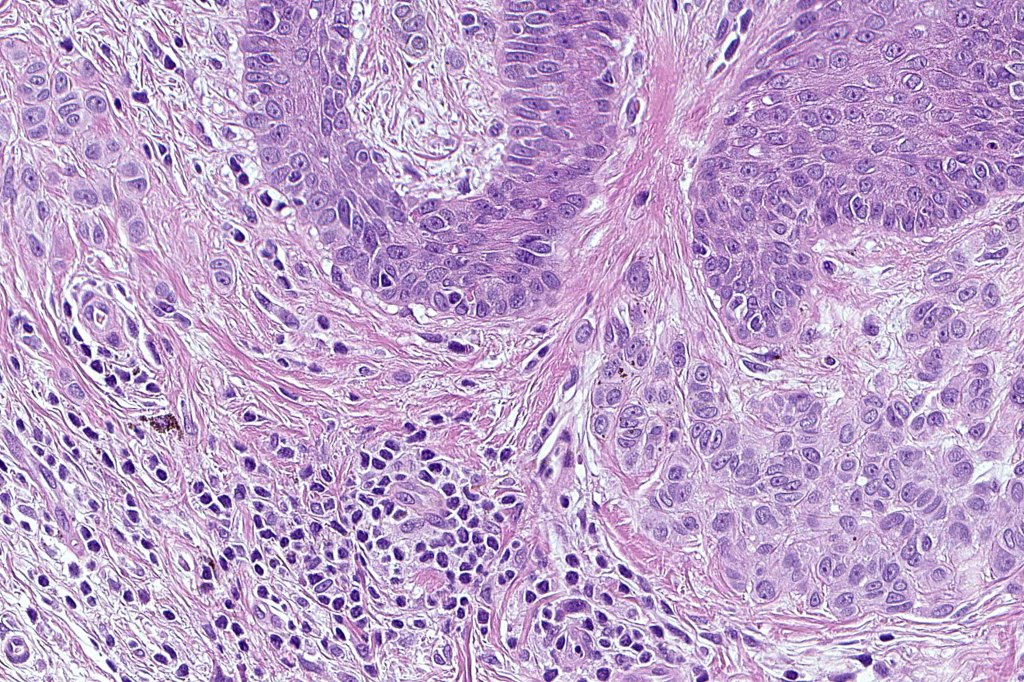

•Cytological atypia- mild, moderate & severe (or more recently, low & high grade (WHO). The problem with the new WHO classification is that mildly dysplastic nevi are now included with the banal nevus category and moderate is low grade and severe is high grade. In all likelyhood, most pathologists will include mild & moderate atypia in the low grade category.

•Variation in the degree of atypia within any one lesion is commonly present

•Rare mitoses

•Pagetoid spread absent

•In compound lesions, the nest size should be smaller than the junctional ones and the degree of atypia the same or less